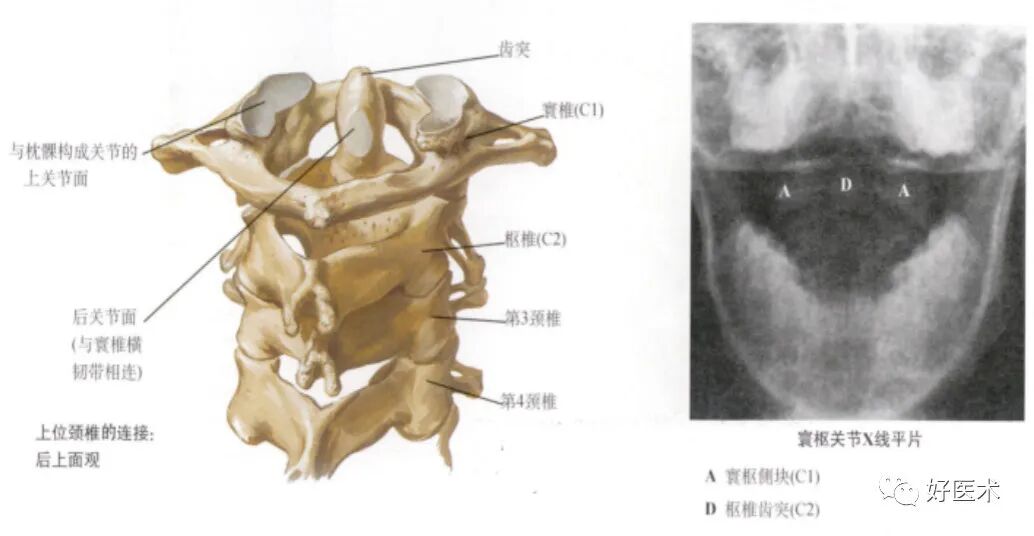

A.上颈椎:

颈枕关节——无间盘

寰椎 (C1)——与颅骨 (C0) 和枢椎 (C2)形成关节

寰枢关节——无间盘

枢椎 (C2)——与C1和C3形成关节

寰椎:

呈环状,无椎体

第2~6颈椎的棘突较短,末端分叉,第7颈椎棘突长,末端不分叉

寰枢关节:

在寰枕连接部,大部分运动功能为前屈—后伸和侧屈

在寰枢关节,近50%的头部旋转运动发生于此

寰枢关节稳固性的结构:关节囊、寰枢前膜、寰枢后膜、覆膜、寰椎十字韧带、齿突尖韧带、翼状韧带等。

枢椎 :

齿状突——寰椎的旋转中心

横突——横突孔、椎动脉、神经根沟

侧块,较大

关节面

棘突 (分叉)